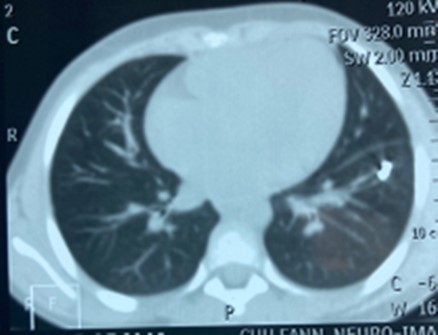

AD, aged 10, with no particular pathological history, was referred to us for the management of a post-traumatic intrapulmonary foreign body. The traumatism would have occurred one month earlier, during a playful accident. He would have received from his brother, at the level of the left hemithorax, a blow with the metal tail of a comb. The latter would then have been torn off by the child but without the tail. This would have caused a minimal wound, associated with an intense chest pain, without dyspnea, or cough, justifying local care and treatment with analgesics. The incident was withheld from parents. On admission, there was a punctiform scar in the 2nd left intercostal space, about 5 cm from the sternal border. The pulmonary fields were free. The rest of the exam was normal. The biological results were normal. A first chest x-ray showed a metal rod, oblique downwards, backwards and inwards, going from the 5th to the 11th left costal arch (Figure 1). The computed tomography scan of the chest showed the metal rod in the lung parenchyma. It was approximately 105 mm long and stayed away from the heart and the great vessels. There was no pulmonary parenchymal abnormality, pleural effusion or obvious bone lesion (Figure 2). Two subsequent X-rays showed its migration downwards, inwards and backwards with an upper pole sitting opposite the posterior arch of the 8th rib. A left posterolateral thoracotomy approach allowed the removal of the metal rod lodged in the lower lobe of the lung (Figure 3). The postoperative period was unremarkable. The ablation of the drains was carried out on the5th postoperative day. The patient was discharged on the 8th day. Reviewed in the6th postoperative month, his examination was normal.

Figure 2.Foreign body in the left lower pulmonary lobe